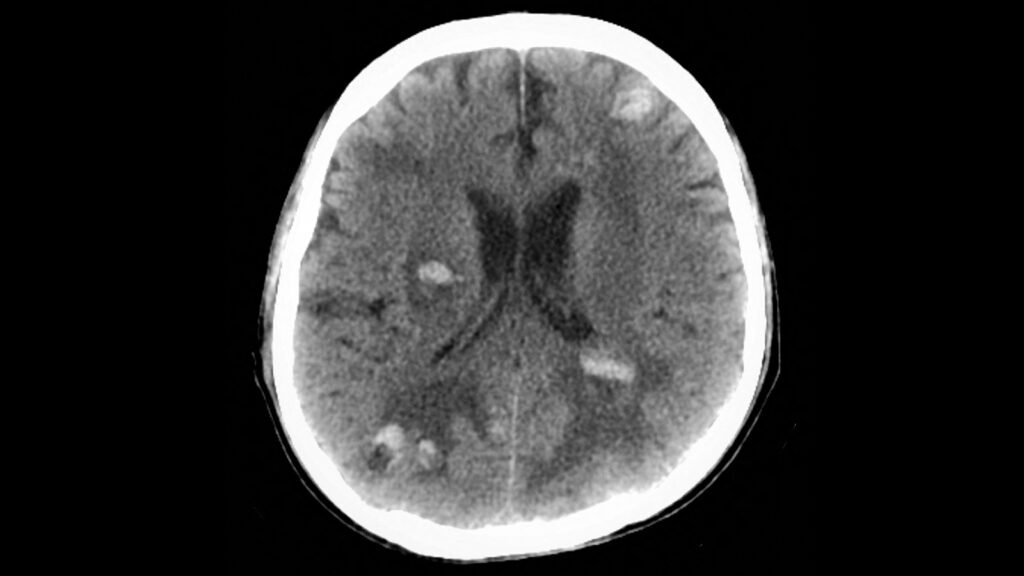

GLP-1 Drugs May Benefit Cancer Patients With Brain LesionsGLP-1 Drugs May Benefit Cancer Patients With Brain Lesions

(MedPage Today) — GLP-1 receptor agonist use was associated with a lower risk of death in cancer patients with brain metastases and type 2 diabetes, a retrospective cohort study found. Within 3 years of a first recorded brain metastasis, patients… (MedPage Today) — GLP-1 receptor agonist use was associated with a lower risk of Read More